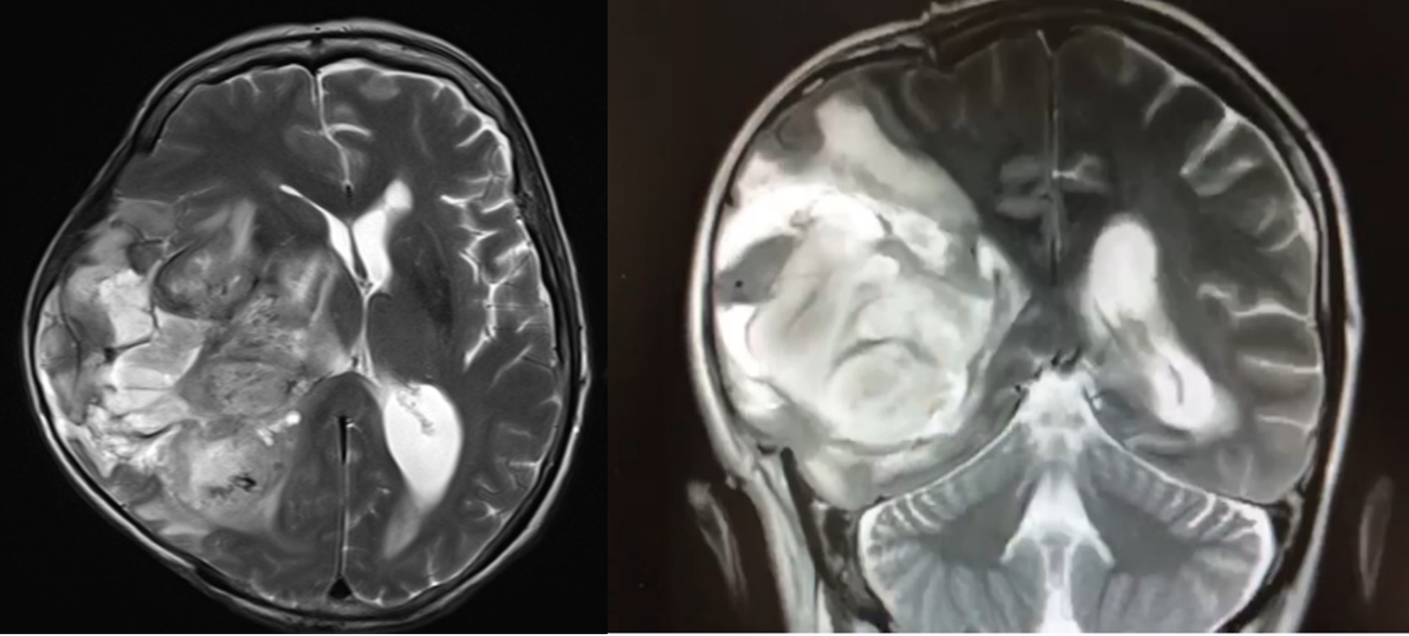

Doente do sexo feminino de 59 anos, não hipertensa, previamente autónoma nas atividades de vida diária e cognitivamente íntegra. Foi admitida no Serviço de Urgência no contexto de cefaleia intensa súbita, apresentando um quadro de hemianopsia homónima e hemiparésia esquerda. Na tomografia computorizada foi identificada uma volumosa hemorragia parenquimatosa cortico-subcortical temporo- fronto-parietal direita. Foi submetida a craniectomia descompressiva emergente. Apresentou, posteriormente, uma evolução clínica e funcional favorável, tendo sido transferida ao 66o dia para enfermaria de MFR. 17 dias depois, iniciou um quadro indolente de deterioração do estado de consciência, com progressiva sonolência e prostração, inviabilizando a participação no programa de reabilitação. Dado o agravamento do estado neurológico, foi realizado novo estudo neuro-imagiológico, o qual identificou uma volumosa lesão expansiva com padrão de realce necrótico-quístico, de provável etiologia neoplásica (primária da série glial ou secundária).

A avaliação, interpretação e orientação de casos de hemorragia intracerebral não traumática com flutuação do estado neurológico e/ou estagnação da evolução funcional na fase subaguda e crónica afigura-se como um desafio diagnóstico. É essencial aumentar a perceção de que quadros de hemorragia intracerebral sem etiologia definida podem ser devidos a neoplasias cerebrais primárias ou secundárias, os quais necessitam de uma avaliação e orientação precoce e dirigida.